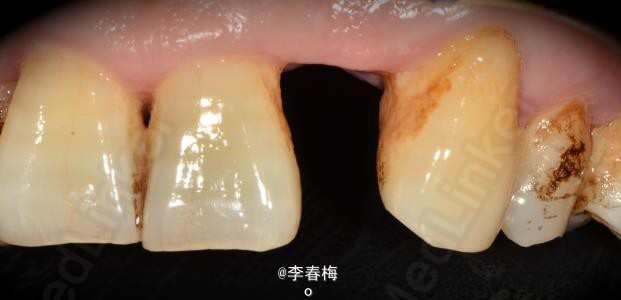

上颌前牙种植修复

患者,男,左上颌侧切牙缺失来诊。平素体质一般,无药物、食物过敏史,无高血压、心脏病等系统性疾病。